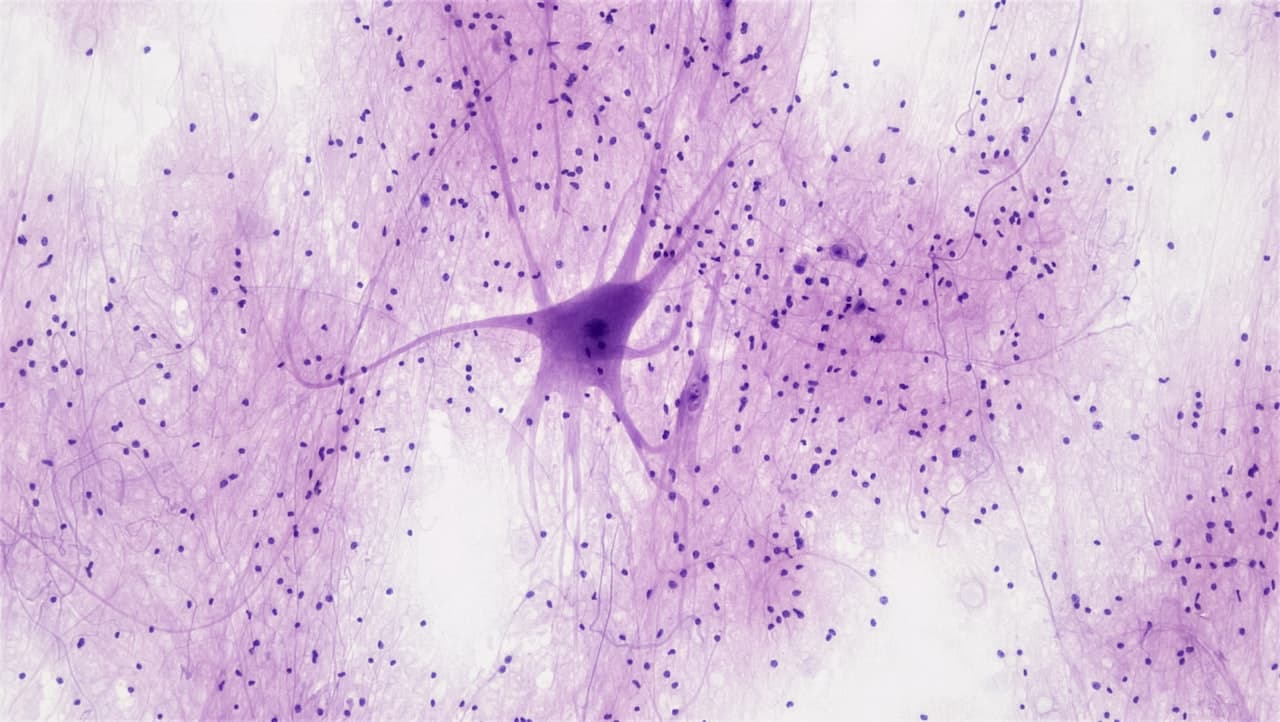

Neuroscience

Psilocybin & Neuroplasticity: An AI Research Overview

An AI-generated audio deep-dive into emerging research on psilocybin's role in promoting structural and functional neuroplasticity — including synaptogenesis, default mode network disruption, and what brain imaging studies reveal about lasting therapeutic effects.